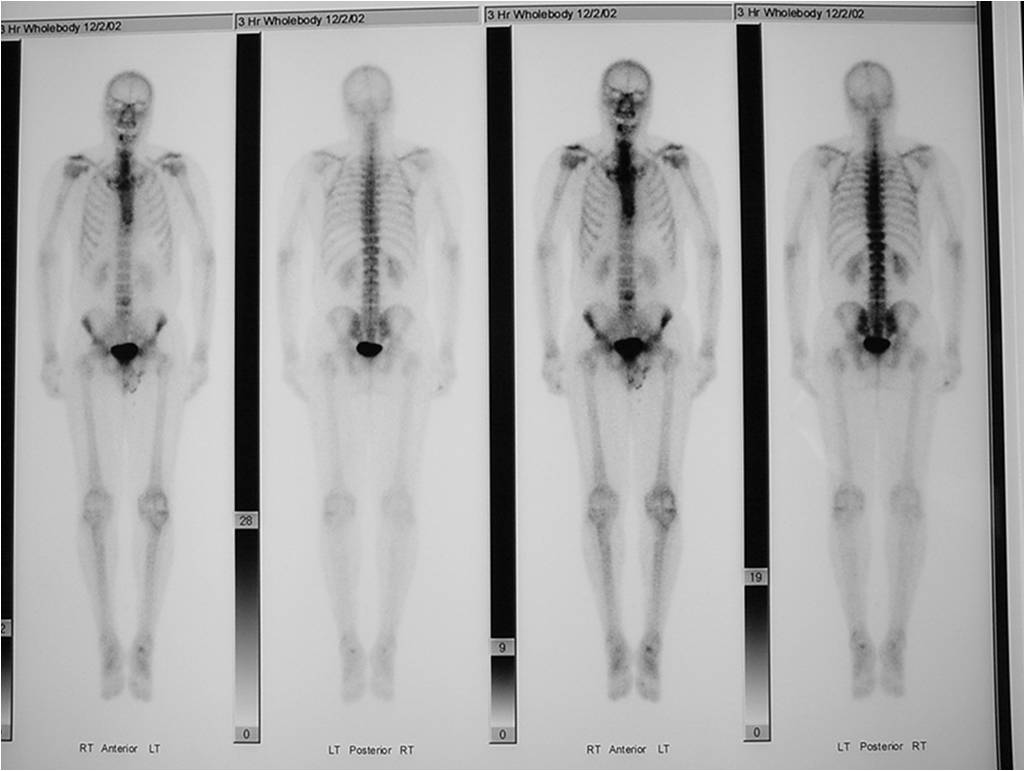

Enchondromas demonstrate increased uptake on a bone scan Most benign cartilage tumors demonstrate uptake that is less than the normal uptake in the ASIS although some may have higher uptake than ASIS

- Bone Scan: Lesion that is hotter than ASIS